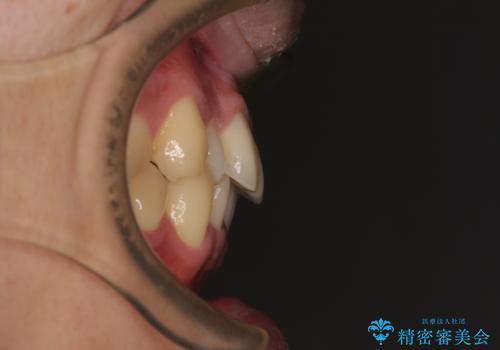

- 上下前歯の捻れやデコボコを気にして来院された患者様です。

マウスピース矯正でもワイヤー矯正でも対応可能でしたが、極力楽をして治したいとのことでワイヤー装置にて治療をおこなうこととしました。

口元はそれほど突出しておらず、患者様自身も気にしていらっしゃいませんでしたが、前歯の捻れやデコボコを解消すると、前方に拡大され、治療後に出っ歯仕上がりとなるリスクがあったため、補助装置により上顎臼歯を後方移動していくこととしました。